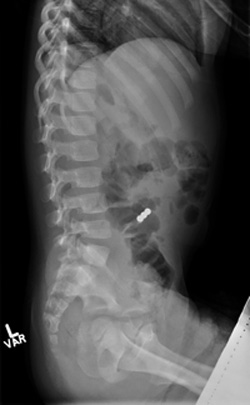

X ray showing a spine with a small bright spot inside the rib cage.

X-rays show a young child who swallowed three small magnets. Surgery was needed to remove the magnets.